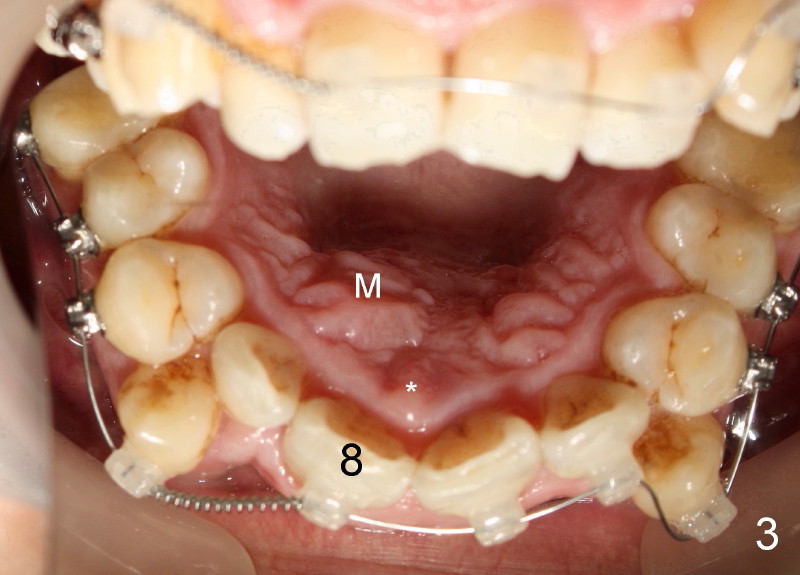

Crown of mesiodens (M) may be oriented toward apically (Fig.1), coronally (Fig.2) or palatally (Fig.4 axial section of CBCT). A common characteristic of mesiodens is that it does not cross midline suture (Fig.1,2 black arrowheads, Fig.4 white arrowheads), although it can push and deform midline suture (Fig.1,2,4 red arrowheads).

How does this happen? Here is a hypothesis. Fig.6A diagrammatically shows the developing premaxilla, which consists of the right and left portions, separated by the midline suture (solid arrow) and the incisal canal (I). As well-known, the developing deciduous incisor tooth buds (A, B) give rise palatally to permanent tooth buds (1,2), respectively (open arrows). For unknown reasons, the developing permanent central incisor tooth bud produces medially an extra tooth bud (mesiodens, green circle in Fig. 6B). The cortices of the developing midline suture appears to be a barrier for the developing mesiodens. Unlike deciduous or permanent teeth, the development mesiodens apparently does not have its definitive growth pattern (probably due to its absence of deciduous precursor). It may grow upward (Fig.1), downward (Fig.2) or palatally (Fig.4,6C) along suture cortex.